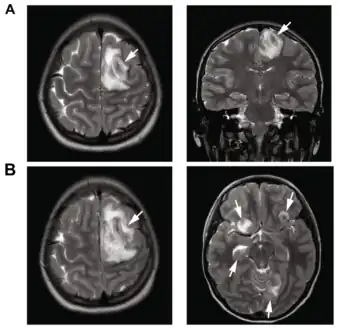

Image of granulomatous amoebic encephalitis caused by Acanthamoeba

A: T2-weighted MRI showing liquefied, necrotic brain tissue as a result of GAE caused by Balamuthia mandrillaris

B: T1-weighted MRI showing expansion and addition of necrotic areas 4 days later